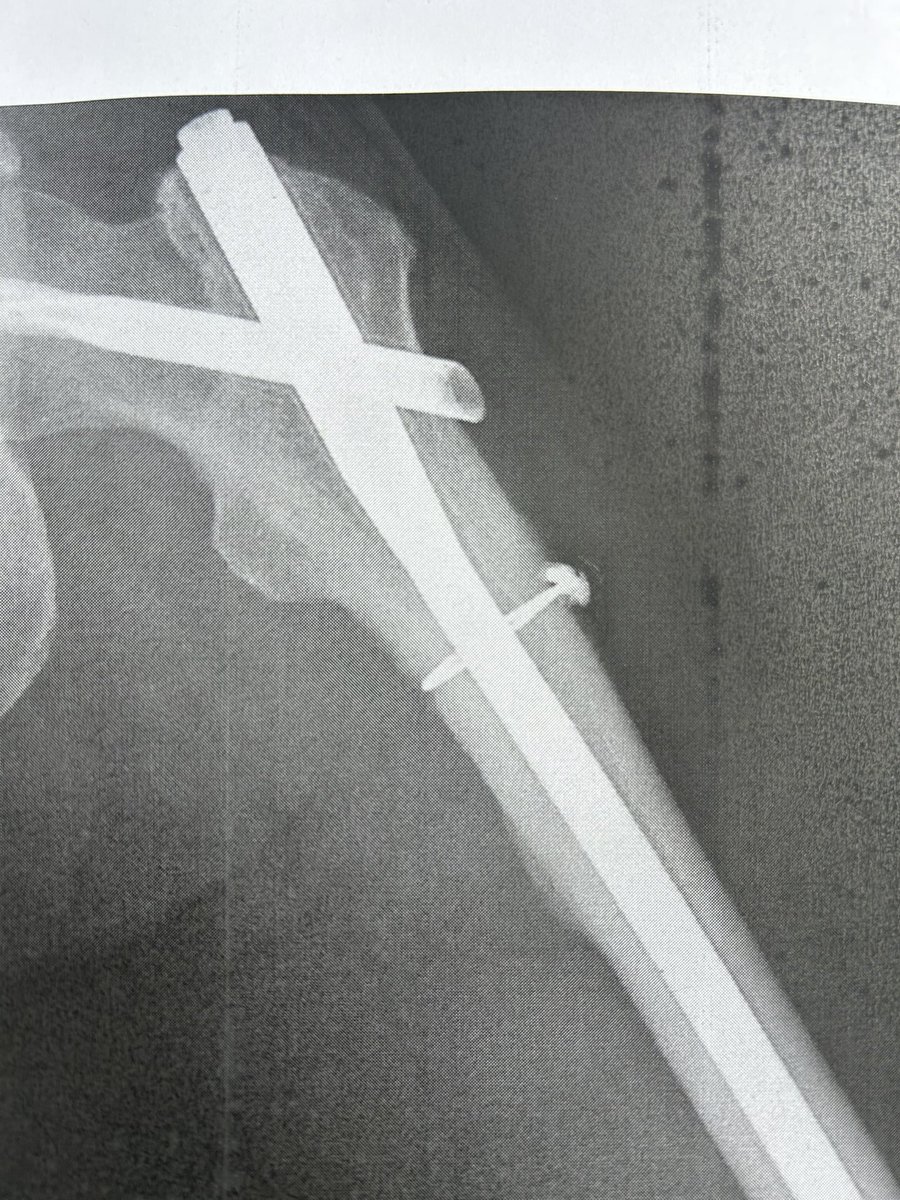

主に自転車&その他趣味(漫画&アニメ)アカ。デブは嫌なので3本ローラーで痩せようともがく引き篭もりのオッサン。650c難民。 2025/3/23落車し大腿骨骨折してリハビリ中〜